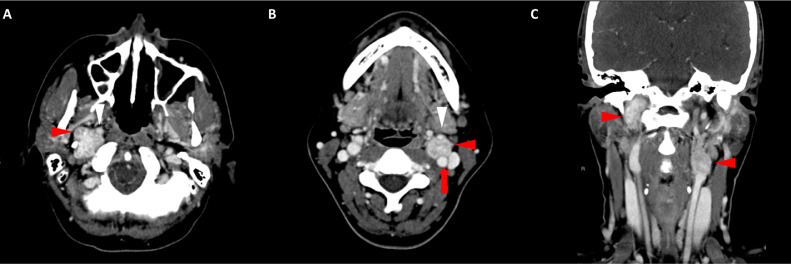

颈部增强 CT 显示 2 个强烈强化的肿块。 一个位于颈部右侧,位于右侧颈内动脉后方的颈动脉间隙中,位于茎突内侧,大小为 24 × 24 × 30 mm,颈静脉横向移位(图 1A)。 第二个位于左侧颈动脉间隙,在分叉处正上方展开颈外动脉和颈内动脉,尺寸为 15 × 18 × 22 mm(图 1B)。 影像学检查结果与右侧迷走神经和左侧颈动脉体副神经节瘤一致,与之前的活检结果一致。